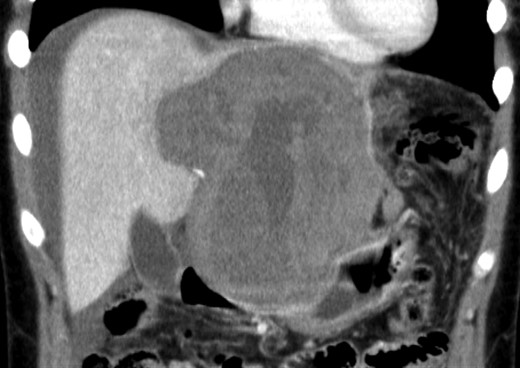

An 18-year-old woman presented with epigastric pain that started during a Japanese drum lesson. She was diagnosed with rupture of a hepatic tumor and transported to our hospital. She had no medical history of surgery, including abdominal surgery. Contrast-enhanced computed tomography (CT) revealed a 13-cm, low-density giant mass in the left hepatic lobe and high-density ascites, indicating abdominal bleeding from the liver tumor (Fig. 1). Ultrasonography confirmed a well-defined giant mass of the liver, comprising both cystic and solid lesions. Laboratory data showed a low hemoglobin level of 8.2 g/dl, and all the results of liver function tests and tumor marker measurement were within normal ranges. The patient underwent emergent celiac angiography, which revealed an avascular tumor with no evidence of extravasation from the hepatic artery. The left hepatic artery was considered to be the artery feeding the tumor and was embolized (Fig. 2). Magnetic resonance imaging (MRI) confirmed a well-defined giant multilocular lesion with fibrous partition (Fig. 3). After the patient's condition stabilized, she underwent left hepatic lobectomy. Laparotomy revealed bloody ascites and a large tumor in the left lobe of the liver; the right lobe appeared normal. The enlarged lymph nodes of the hepatoduodenal ligament were also dissected. Histological analysis of the resected specimen revealed a huge cystic mass of ∼12 × 9.5 cm. The mass was cystic and multilocular with a fibrous wall and filled with a massive blood clot (Fig. 4). The enlarged lymph node had a 25 × 23-mm cyst, which contained yellowish fluid. On microscopic examination, the wall of the cyst consisted of a tight elastic fiber meshwork composed of collagen fibers, which was accompanied by a small amount of acid mucopolysaccharide in the stroma and a lining of single-layered flat cells on the inner wall (Fig. 5a and b). Immunohistochemical staining revealed that the cyst wall was positive for both the endothelial marker CD31 and the lymphangial marker D2-40 (Fig. 5c and d). The cystic structure of the lymph node also was composed of elastic fiber components similar to those of the cyst in the liver and lined with single-layered flat cells, which were immunohistochemically positive both for CD31 and D2-40 (Fig. 5e). The pathological diagnosis was hepatic lymphangioma combined with lymphangioma of the lymph nodes. The patient's postoperative course was uneventful, and she was discharged on Day 8. During follow-up for almost 4 years since the surgical treatment, the patient has presented no sign of recurrence.

Enhanced CT scan demonstrated a low-density giant mass 13 cm in size and high-density ascites.